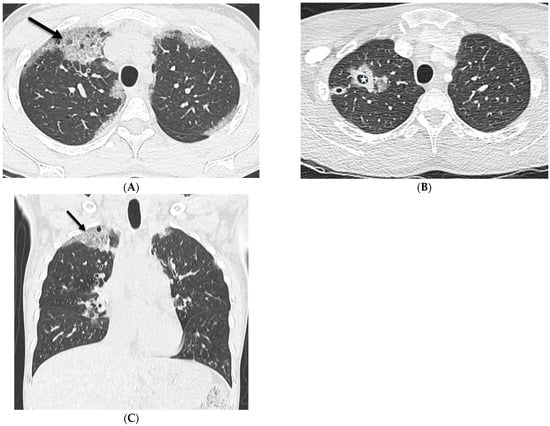

5.1. Invasive Lung Adenocarcinoma

5.2. Kaposi’s Sarcoma